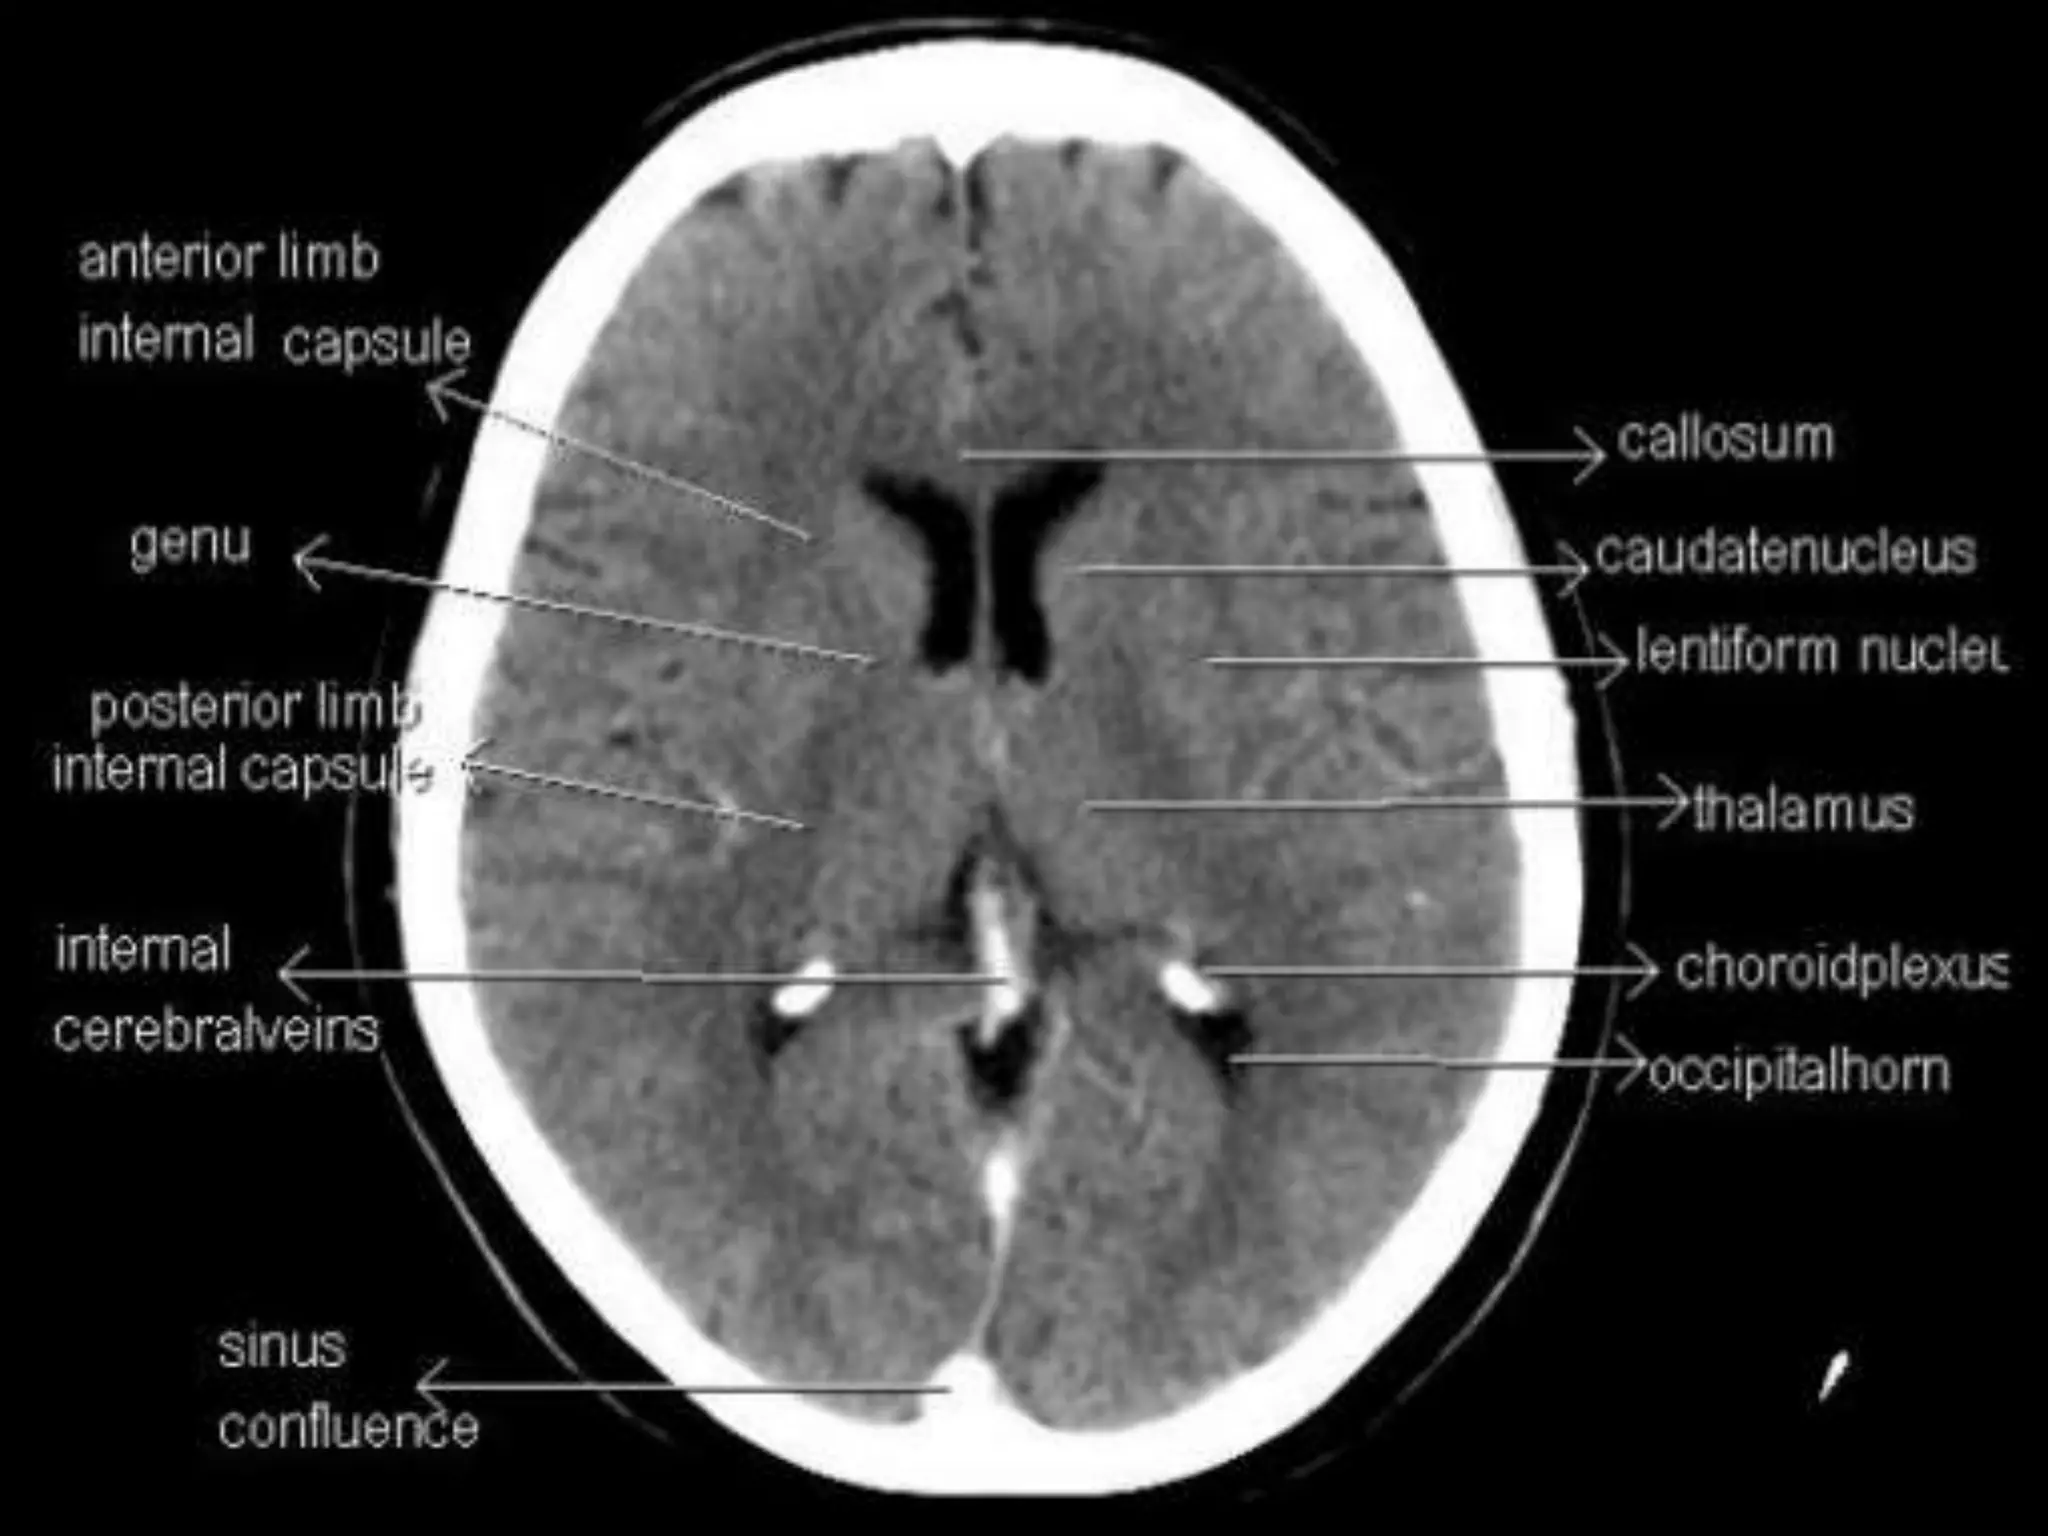

Axial CT Anatomy.

Sectional Anatomy: NormalAxial CT and MRI Anatomy. On CT and MR scans, the brain has been briefly viewed in infratentorial and supratentorial sections, as described below. CT scans are performed with a 15- to 20-degree angulation to the canthomeatal line at 8-mm increments. MRI scans are generally obtained parallel to the AC-PC line in the axial plane with 6-mm slice thickness. Using the sagittal view, the coronal sections are acquired parallel to the brain stem, and the sagittal sections are obtained perpendicular to the axial section. On MRI studies, cranial nerves IX and X can be demonstrated at this level because they emerge from the postolivary sulcus. The posterior aspect of the cerebellar hemispheres is outlined by the inferior portion of the cisterna magna.